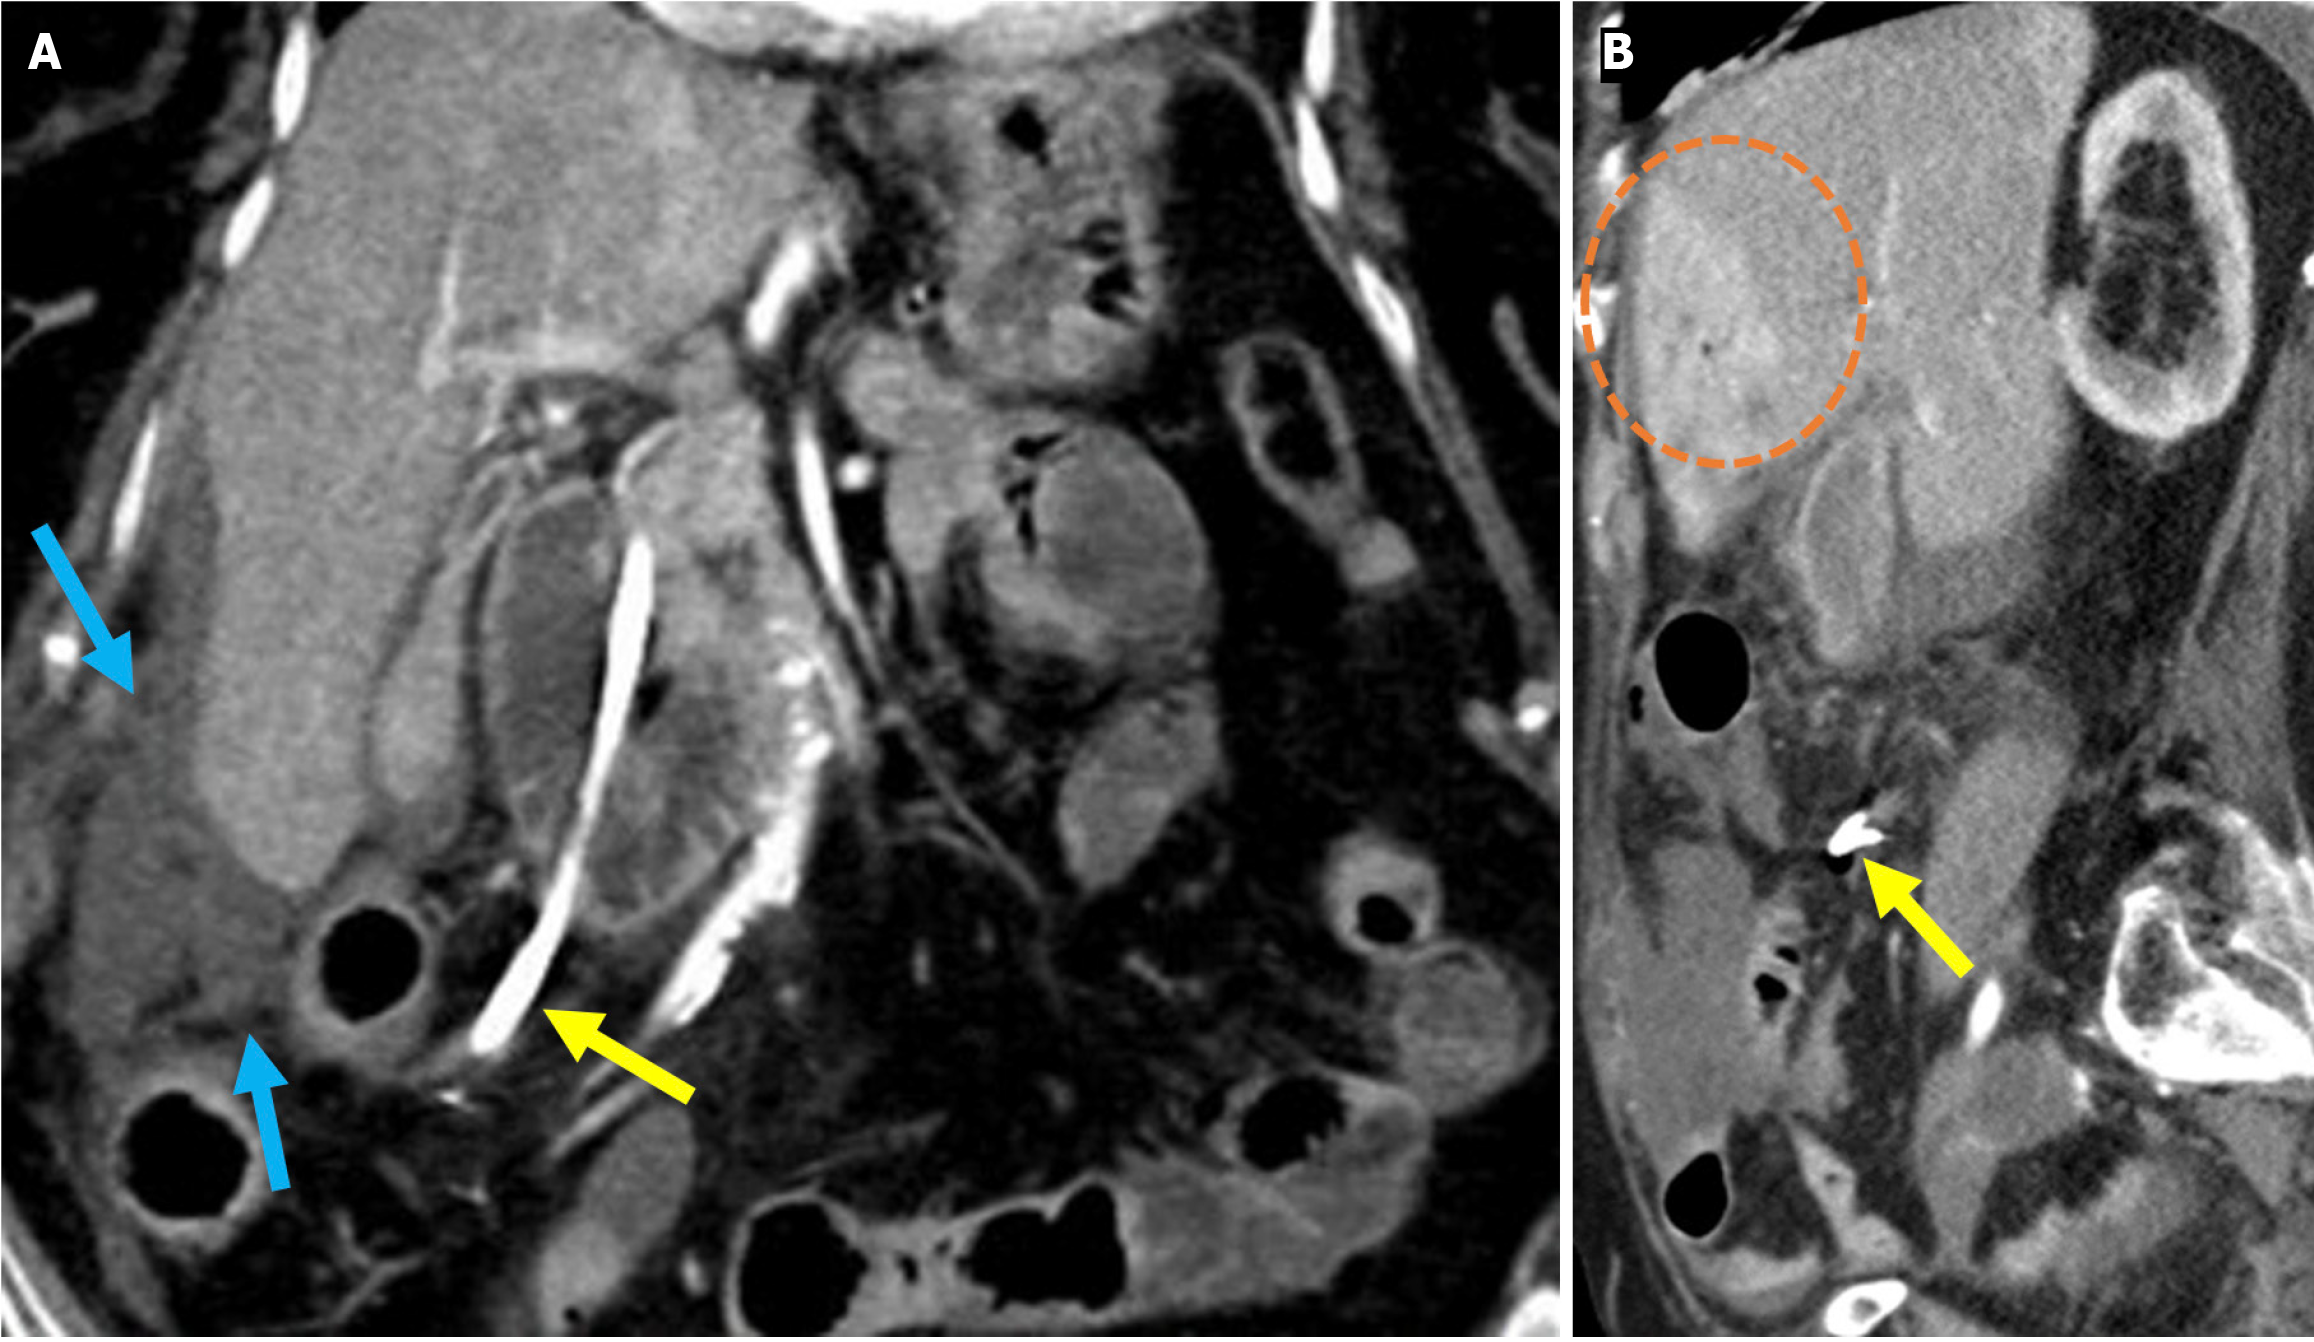

The revised Atlanta classification recognizes two primary forms of acute pancreatitis: NP and interstitial edematous pancreatitis (IEP). NP tends to follow a more severe clinical course with higher rates of infection, organ failure, and mortality. Imaging reveals hypoperfused or non-enhancing areas indicating NP or peripancreatic necrosis. Early collections (within 4 weeks) are referred to as acute necrotic collections. Once encapsulated after 4 weeks, they are known as walled-off necrosis (Figure 3)[23]. IEP is characterized by a diffusely enlarged pancreas with homogeneous enhancement on CECT imaging without areas of necrosis and with peripancreatic fat stranding and fluid accumulation. Fluid collections observed within the first 4 weeks are termed acute peripancreatic fluid collections, while those persisting beyond 4 weeks are classified as pancreatic pseudocysts (Figures 4 and 5).

Figure 4

Figure 4 Interstitial edematous pancreatitis and acute peripancreatic fluid collections. A-C: Contrast-enhanced coronal and axial computed tomography (CT) images (A and C), coronal T2-weighted magnetic resonance imaging (B); D: Fat-suppressed axial T2-weighted magnetic resonance imaging. The 81-year-old female patient diagnosed with post-endoscopic retrograde cholangiopancreatography pancreatitis had presented with epigastric pain and elevated amylase and C-reactive protein levels. CT images showed preserved pancreatic enhancement that was consistent with the absence of necrosis and peripancreatic fat stranding (blue arrow). The pancreatic enlargement and increased T2 signal intensity were suggestive of edema (purple arrow). The pancreas also exhibited mildly diffuse, lace-like T2 hyperintensity within the parenchyma that was associated with a small acute peripancreatic fluid collection (yellow arrow).

Figure 5

Figure 5 Acute peripancreatic fluid collections and pseudocyst. A: Noncontrast axial computed tomography (CT); B: Contrast-enhanced axial CT after 15 months. A 28-year-old female patient underwent endoscopic retrograde cholangiopancreatography for choledocholithiasis. Ten hours after the procedure, the patient developed severe upper quadrant abdominal pain accompanied by fever. No signs of peritonitis were observed, and there was no evidence of hemodynamic instability. Laboratory tests revealed elevated levels of pancreatic enzymes and inflammatory markers. Due to suspected pancreatitis a noncontrast CT performed on post-procedure day 1 (A) demonstrated fluid loculation in the infrahepatic and paraduodenal region that was consistent with acute peripancreatic fluid collections (yellow arrow). The patient was diagnosed with post-endoscopic retrograde cholangiopancreatography edematous pancreatitis and was managed conservatively. A follow-up contrast-enhanced CT performed 1.5 months later (B) showed fluid collection in the exact location with pseudocapsule formation that was consistent with a pseudocyst (blue arrow).